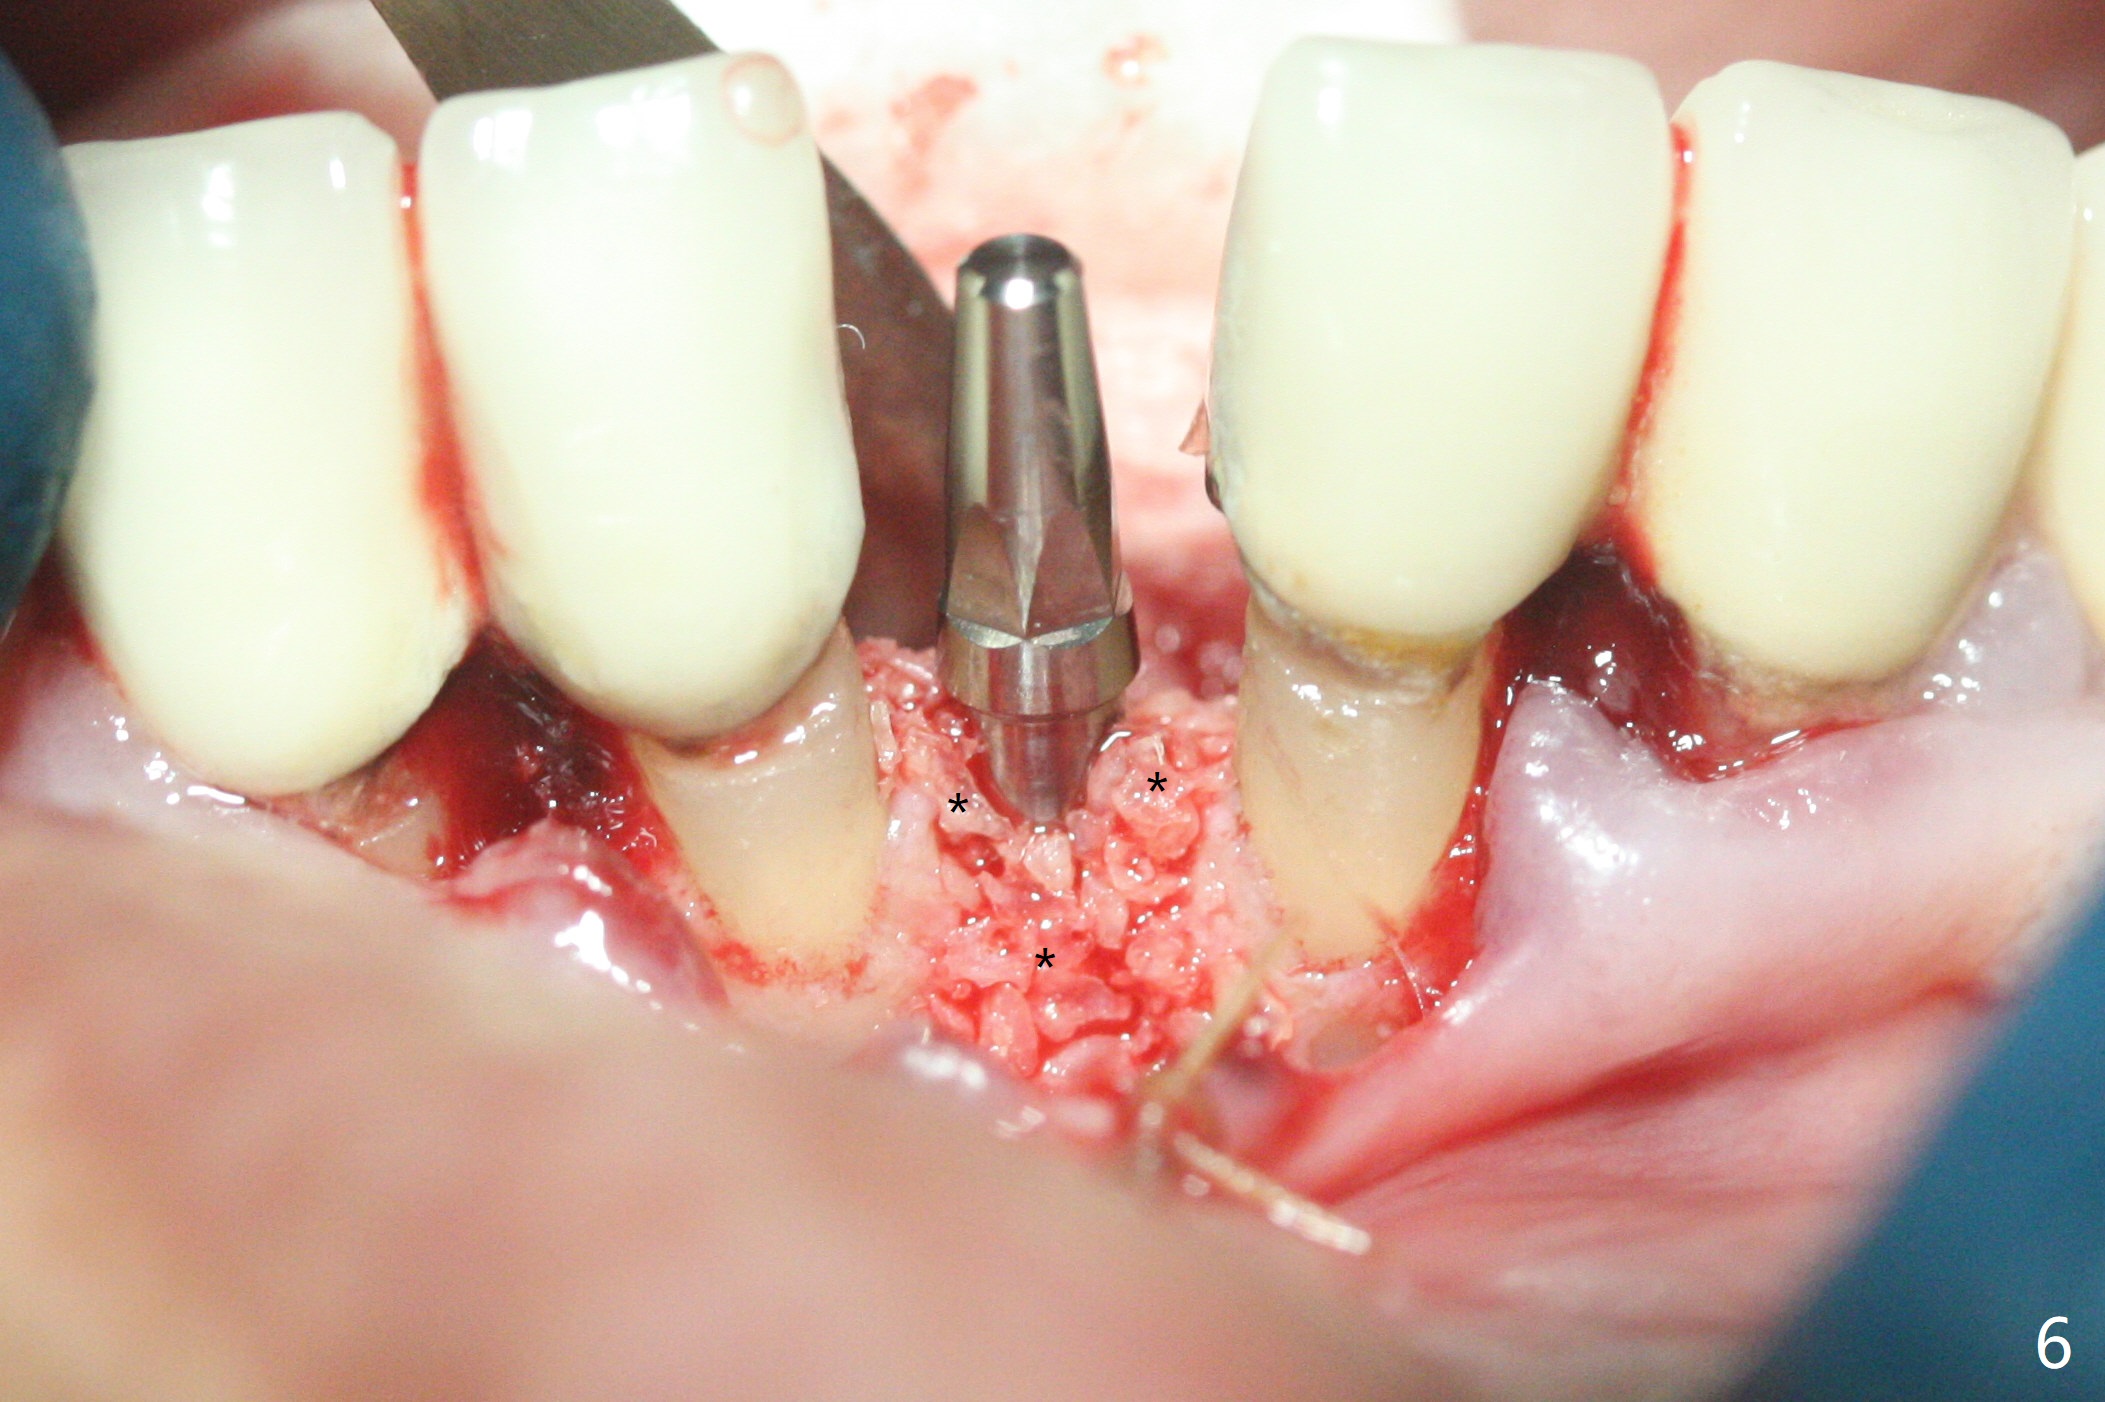

种植前与66岁女病人再次讨论下前牙正中种植可能产生不对称问题,她好像不在乎。术前检查显示下前牙正中间隙偏左(图一),处理似乎容易,但是牙槽嵴相当狭窄(图一 *,二 箭头)。牙槽嵴切除后(大约3 毫米宽(颊舌侧)),初期钻洞似乎偏移右边(图三),矫正后(图四),植入2乘10(4)毫米连体植体(图五,比预计小,因为骨质薄),放置骨粉(图五,六 *)和膜,缝合,制作即刻修复物(图七 T),病人满意,牙槽骨饱满了。术后一个多月临时牙冠取出修正,伤口愈合,由于植骨颊侧没有凹陷(图八),而舌侧隆起(图九:*,与图二术前对比)。其实病人不小心吃牛肉时损伤植体,疼痛几天。尽管最近吃饭时植牙又受伤,但是没有松动,也没有骨质吸收,就是局部结石多(图十,术后四个月)。正式牙冠术后4.5个月粘固(图十一)。